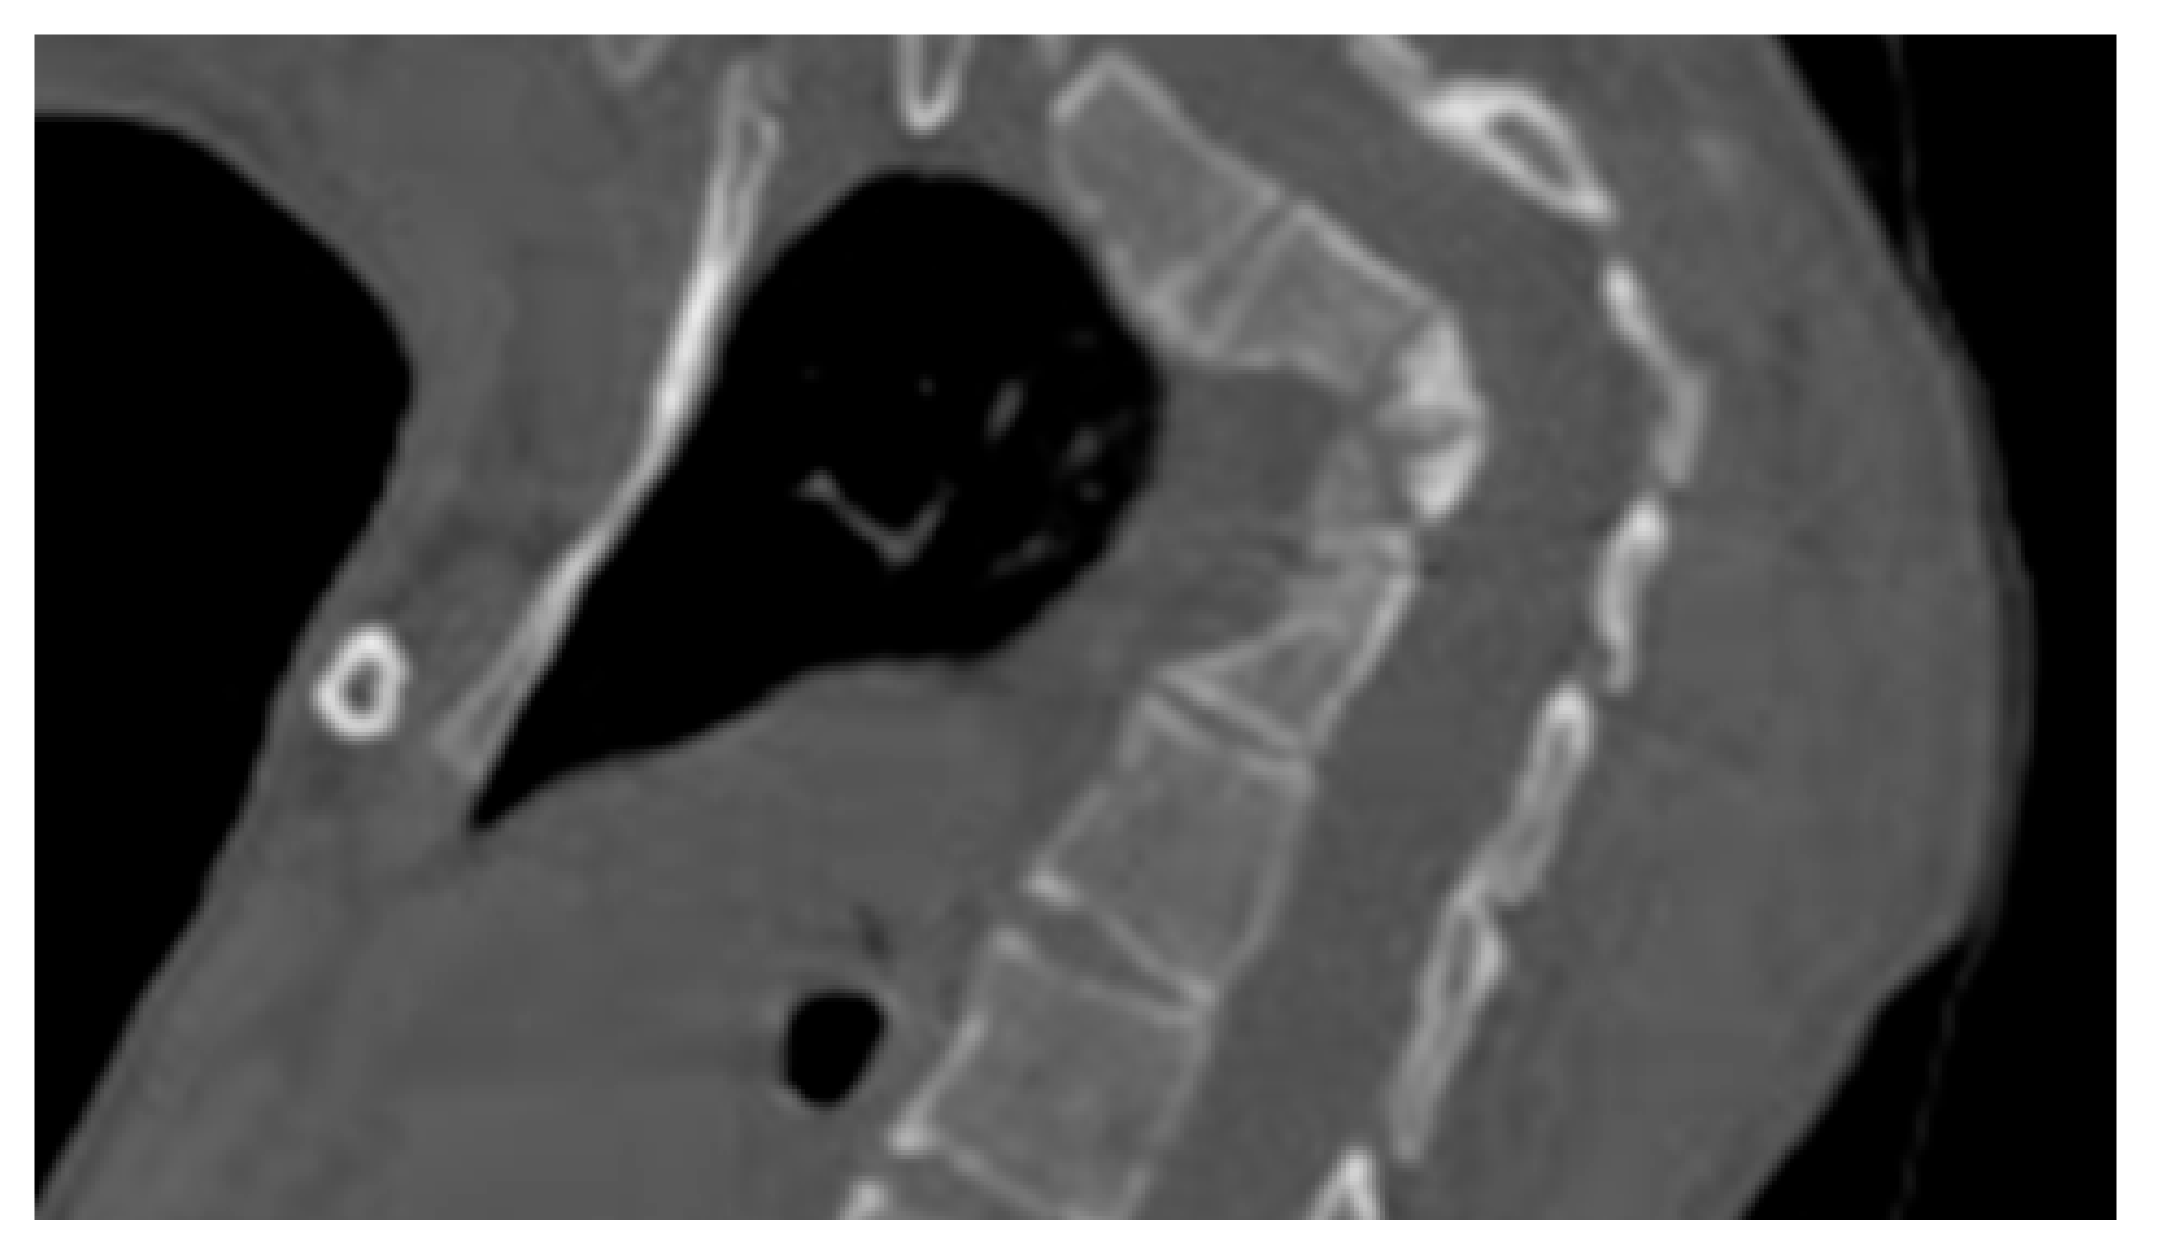

- A ten-year-old-girl presented with painful acute upper thoracic kyphosis. Radiographs of the spine were difficult to assess. 3D reformatted CT scan of the thoracic spine showed progressive osteolysis of T3-T6 (Figure 2). Skeletal survey did not show any other involved areas.